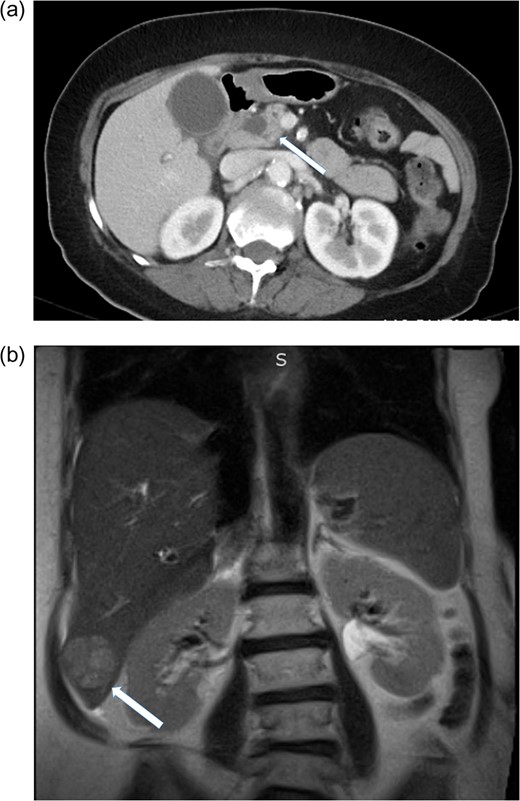

A 70-year-old woman presented with right-sided abdominal pain, nausea, vomiting and fever. She had a history of diabetes, hypertension and hypercholesterolemia. She smoked 0.5 pack/day and denied alcohol abuse. There was no significant family history. On admission her vital signs were within normal limits. On physical exam her sclera were anicteric. Her abdomen was soft, non-tender, non-distended with no palpable masses. Labarotory studies revealed: Alk Phos 126 IU/L, total bilirubin 2.0 mg/dL, AST 63 IU/L, ALT 58 IU/L, tumor markers showed AFP 226 ng/mL (normal 0.0–8), CA 19-9 959 unit/mL (normal 0–35) and carcinoembryonic antigen (CEA) 3.9 ng/mL (normal 0–3). Hepatitis C antibody was reactive and Hepatitis B core AB negative. CAT-scan of the abdomen revealed a 1.3 cm mass in the head of the pancreas with intrahepatic and extrahepatic ductal dilatation (Fig. 1a). MRI of the abdomen showed a 3.7 cm mass in segment VI of the liver (Fig. 1b). ERCP with bile duct brushings was performed and consistent with malignancy. EUS demonstrated a 2.6 cm mass in the head of the pancreas with portal vein involvement. Ultrasound guided biopsy of the liver was consistent with HCC. (Fig. 2). Routine staging CT scan of the chest showed a prominent 2.1 cm pre-tracheal lymph node. Endobronchial ultrasound guided-fine needle aspiration (FNA) of this lymph node showed no evidence of malignant cells.

(a) CT scan of the abdomen showing pancreatic mass, solid arrow. (b) MRI of the abdomen showing segment six hepatic lesion, solid arrow.